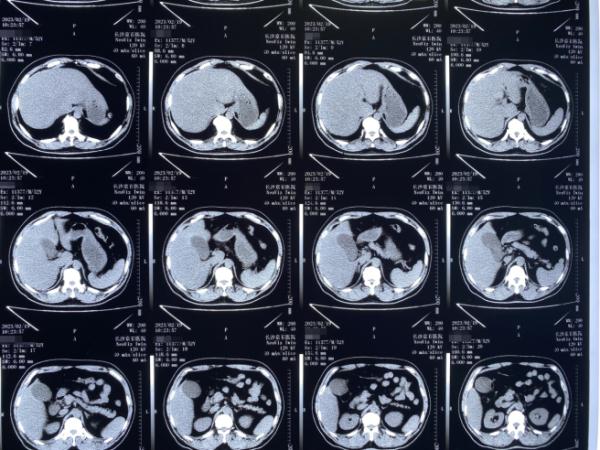

赵先生术前CT检查结果局部图

2月19日,赵先生在医院接受了初步的检查,确诊患有胆囊多发结石并胆囊炎,已达到手术治疗指征,于是赵先生立即办理了入院手续,准备接受手术治疗。

据长沙京石医院肝胆外科主任李小攀介绍:“患者的结石属于多发性的,数量比较多,而且结石比较小。像这样的结石如果不尽早处理,一旦结石嵌顿在胆囊颈部或者胆囊管,胆囊会迅速失去功能,失去保胆取石的机会。而且小颗粒的结石一旦掉入胆总管,还会继发更为危险、难以处理的胆总管结石。”

因此,在完善各项术前检查之后,医生团队根据赵先生的结石病情及保胆需求,为其制定了超微创经脐无痕保胆取石手术方案。2月20日,医生团队为赵先生顺利进行手术,成功保留下有功能的胆囊,并取出25颗酷似“玉米粒”的小结石。